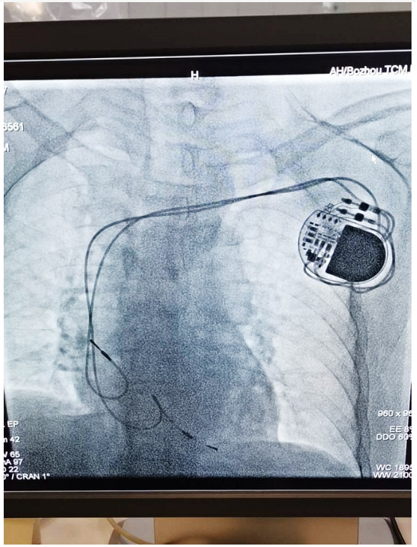

导联相关性静脉狭窄/闭塞(LRVSO): 心脏起搏器、植入式心脏转复除颤器(ICD)等装置导联的植入,会引发内皮损伤、炎症反应和纤维蛋白沉积。随时间推移,导线周围会形成富含胶原的纤维鞘,甚至将多根导线捆绑在一起,导致静脉管腔狭窄或闭塞。

�� 病例二:

术前造影

建立通道

球囊扩张、支架置入